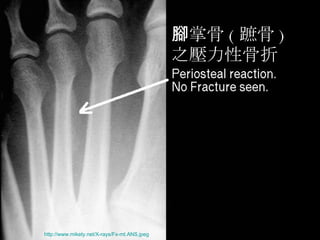

腳掌骨 ( 蹠骨 ) 之壓力性骨折 http://www.mikety.net/X-rays/Fx-mt.ANS.jpeg

壓力性骨折 Stress Fracture 疲勞骨折 Fatigue fracture   骨質不良性骨折 Insufficiency fracture http://www.emedicine.com/radio/topic783.htm